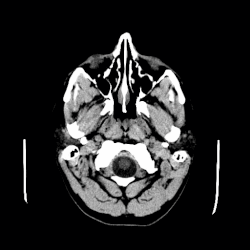

| A CT scan of an arachnoid cyst | |

The diagnostic process typically begins with a medical history workup followed by a medical examination by a physician. Imaging tests, such as CT scans and MRIs, help provide a clearer picture. The physician typically looks for fluid (or other bodily substance) filled sacs to appear in the scans, as is shown in the CT scan of a colloid cyst. A primary health care provider will refer an individual to a neurologist or neurosurgeon for further examination. Other diagnostic methods include radiological examinations and macroscopic examinations. After a diagnosis has been made, immunohistochemistry may be used to differentiate between epithelial cysts and arachnoid cysts.[2] These examinations are useful to get a general idea of possible treatment options, but can be unsatisfactory to diagnose CNS cysts.[3][5] Professionals still do not fully understand how cysts form; however, analyzing the walls of different cyst types, using electron microscopes and light microscopes, has proven to be the best diagnostic tool. This has led to more accurate cyst classification and correct course of action for treatments that are cyst specific. In the past, before imaging scans or tests were available, medical professionals could only diagnose cysts via exploratory surgery.[2]